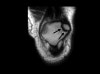

MRI는 전위가 안 된 골절확인에 도움이 됩니다.

MRI : 슬개골 골절(Patellar fracture, Broken kneecap)